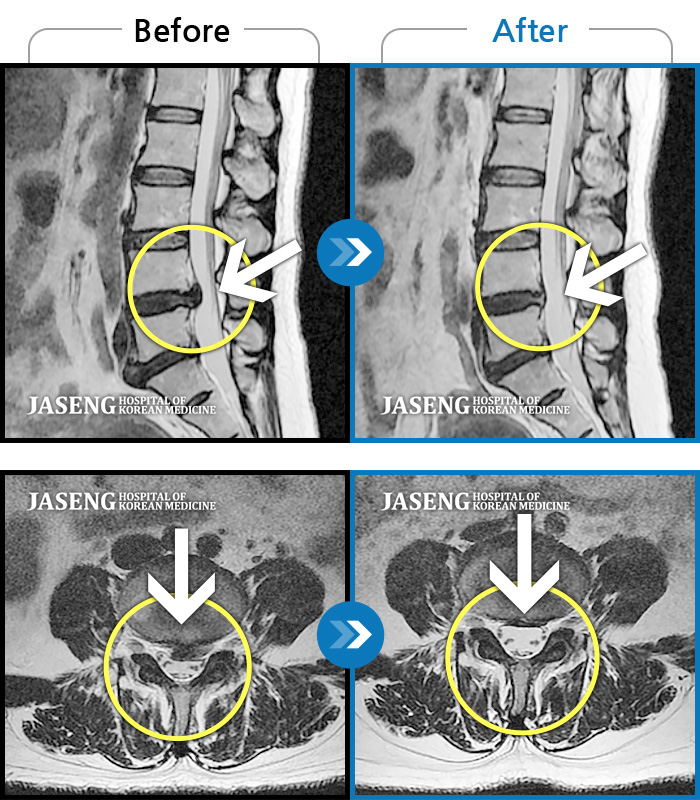

허리디스크

대전 · 김창연 원장

허리랑 좌측 엉덩이가 뻐근하게 많이 아프고, 허벅지와 종아리가 저림이 심해요. 걷기가 힘들어요.

촬영시기

2023.10.30 ~ 2024.07.19

2024.08.09

조회수 526